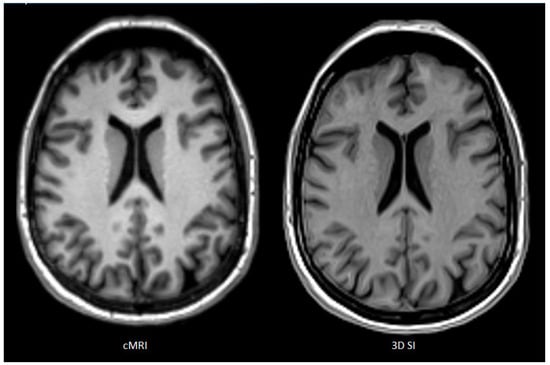

Clinical Image Quality and Reader Variability in 3D Synthetic Brain MRI Compared with Conventional MRI

Background/Objectives: This study evaluated the clinical image quality of three-dimensional synthetic MRI (3D SI) compared with conventional MRI (cMRI), focusing on tissue contrast, anatomical detail, and motion sensitivity. Methods: Patients with nonspecific neurological symptoms were included. Both cMRI and 3D SI were acquired on single-vendor 1.5 T and 3 T scanners with slice thicknesses of 1.0–1.7 mm. Two experienced neuroradiologists and one fellow independently evaluated matched scans using a 0–100 scale. Assessed parameters included signal-to-noise ratio (SNR), gray–white matter contrast, artifacts, motion robustness, and confidence in detecting perivascular spaces, white matter lesions, and subtle pathology. Interrater agreement was measured using Krippendorff’s alpha and ICC2. Multiple linear regression analyzed associations between image quality ratings and imaging method. Results: Images of 31 patients were analyzed. Three-dimensional SI demonstrated sufficient-to-good overall image quality and high robustness to motion. Cortical-surface-to-cerebrospinal-fluid contrast on FLAIR was rated lower for 3D SI than for cMRI. False-positive lesion detection occurred more frequently on 3D SI FLAIR, particularly among experienced readers. cMRI achieved significantly higher T1-weighted SNR than 3D SI (8.76 points, p < 0.001). Experienced readers consistently rated SNR and tissue contrast higher than the fellow. Vascular signal range was broader on 3D SI, reducing sensitivity to vascular abnormalities. Conclusions: Three-dimensional synthetic MRI provides clinically usable image quality and fulfills its primary diagnostic purpose, offering advantages in acquisition efficiency and robustness to motion. Nevertheless, limitations in cortical contrast, vascular signal characterization, and reader-dependent interpretive variability constrain its reliability for subtle or detail-critical findings. Full article